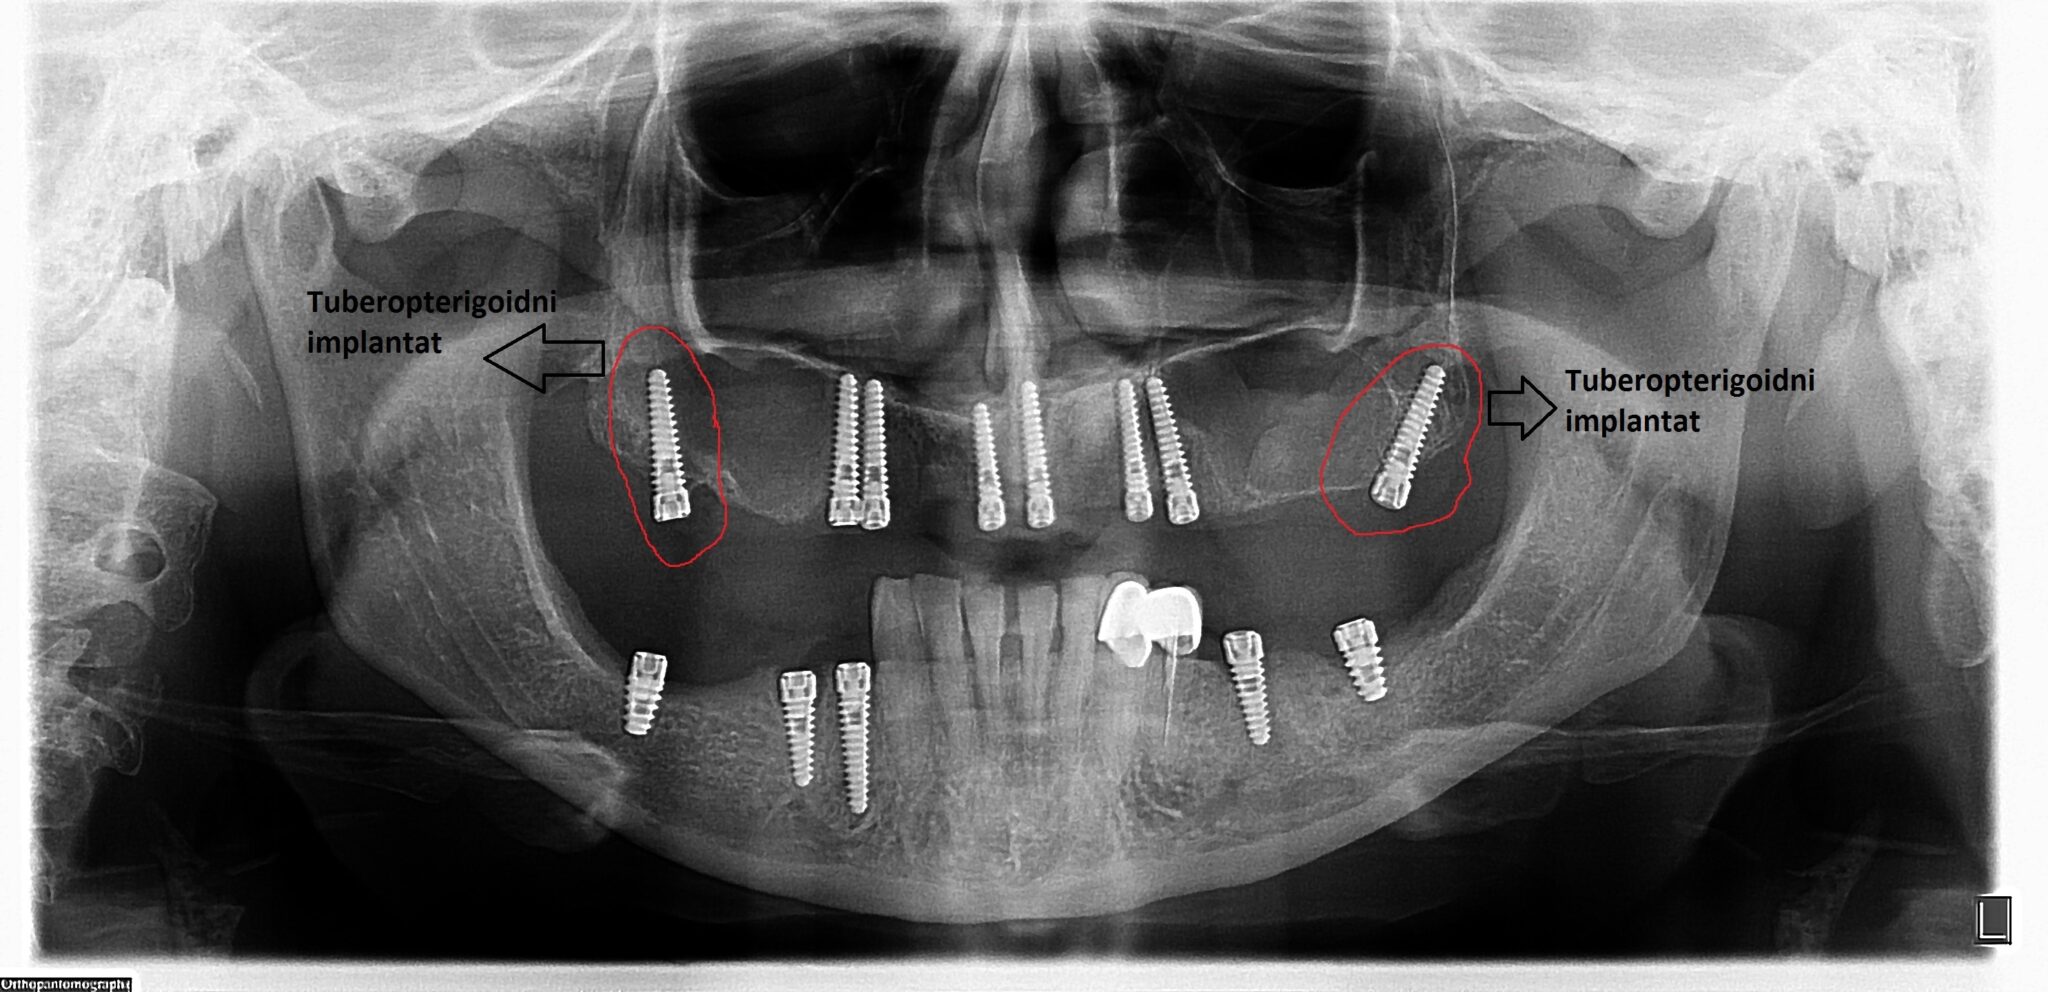

Na slikama su prikzani tubero-pterigoidni implantati postavljeni u cilju da se izbegne sinus lift procedura, čime je omogućena izrada fiksnog protetskog rada, sa kompletanim zubnim nizom, uz minimalnu površinu naleganja na meka tkiva.

Ovaj tip implantata omogućava izbegavanje sinus lift operacije, koja se inače koristi za povećanje koštane mase u predelu maksilarnog sinusa.

Operacija sinus lifta zahteva komplikovanu hiruršku proceduru, a dužina čekanja na definitivni protetski rad na implantatima u toj regiji traje i do dve godine. Ugradnja tuber-pterigoidnih implantata predstavlja relativno jednostavnu metodu, ali zahteva veliko iskustvo, preciznost i temeljno znanje iz anatomije i oralne hirurgije.

Tuber-pterigoidni implantat skraćuje vreme izrade definitivnog rada na implantatima i njime se izbegavaju neprijatnosti posthirurškog toka operacije sinus lifta.